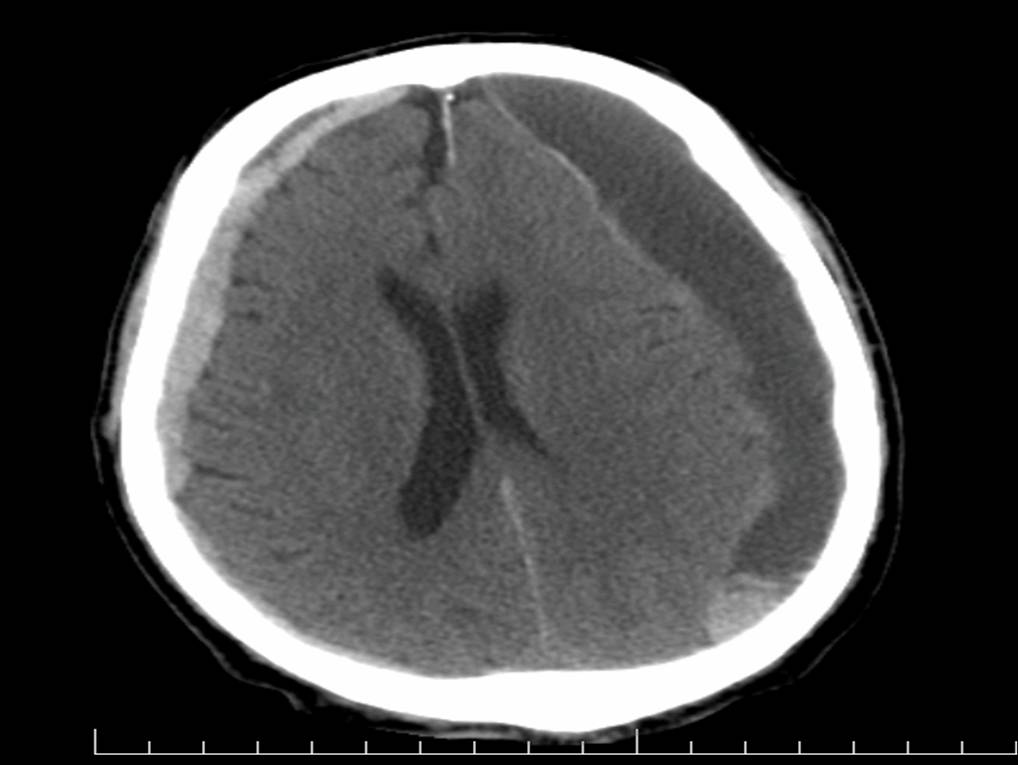

An 8-year-old boy is brought to the pediatrician because of headaches and impaired vision for the past 7 to 10 days. Neurologic examination reveals bilateral temporal visual field defects. The rest of the physical examination is unremarkable. A noncontrast CT scan of the head is shown.

Which of the following laboratory findings is most likely in this patient?

A) Decreased growth hormone level

Craniopharyngioma is one of the most common childhood supratentorial tumors and presents with headaches and bitemporal hemianopia. Craniopharyngiomas may lead to hypopituitarism, including low ADH, TSH, growth hormone, gonadotropin, and ACTH secretion.